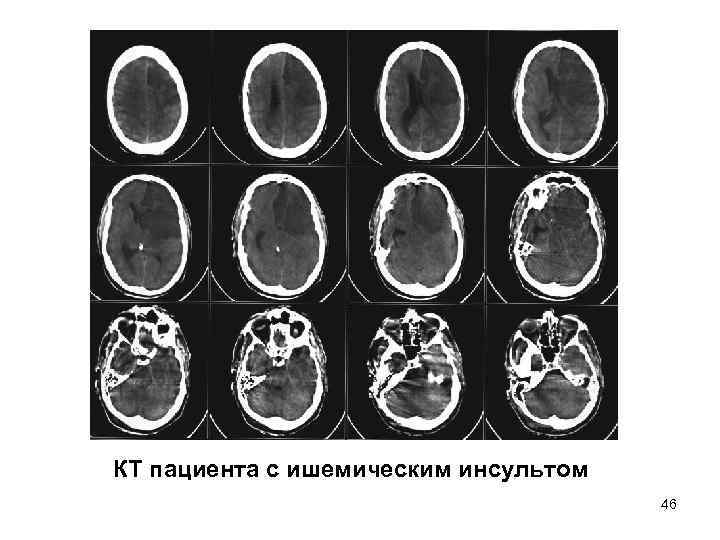

• КТ - 1. структурные аномалии • опухоль, гидроцефалия 2. воспалительные заболевания • абсцесс, энцефалит 3. сосудистые заболевания • кровоизлияние, острая субдуральная (эпидуральная) гематома, ишемический инсульт 4. перелом основания черепа 5. травма мозга 45

КТ пациента с ишемическим инсультом 46